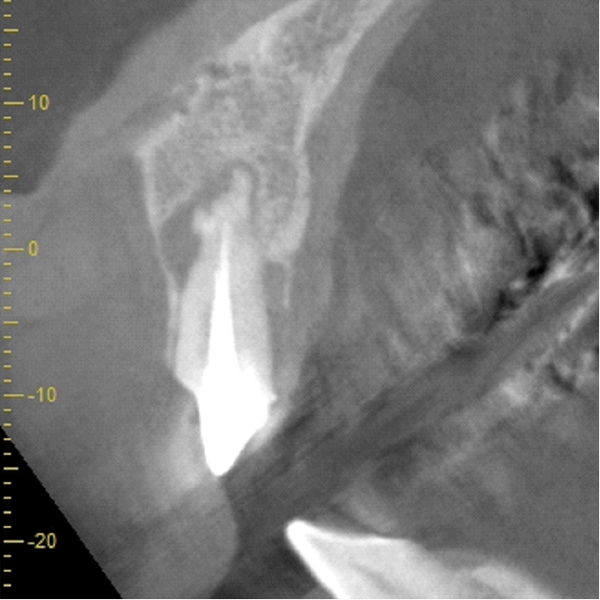

| 年代・性別 | 50代 男性 |

|---|---|

| 主訴 | 前医で前歯を抜かなければならないがインプラントはできないと言われた |

| 治療期間 | 約12ヶ月 |

| 費用 | 600,000円 |

| 治療内容 | インプラント、骨造成、結合組織移植、セラミック修復 |

| 治療に伴うリスク | インプラント周囲炎 セラミックの破折、脱離 |